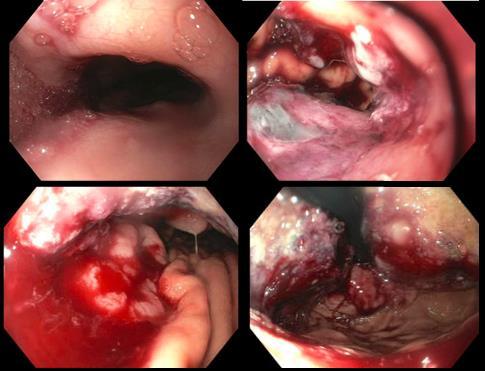

SEVERE GASTROINTESTINAL BLEEDING FOLLOWING TRANSESOPHAGEAL ECHOCARDIOGRAPHY AND ABLATION FOR ATRIAL FIBRILLATION

Christy Chon1 , Frederick Rozenshteyn1, Bruce Gelman1

1Mount Sinai Morningside-West Hospitals, Icahn School of Medicine at Mount Sinai, New York, NY, United States Presented at the American College of Gastroenterology (ACG) Annual Meeting that was held in Charlotte, North Carolina, United States from October 24-26, 2022 15